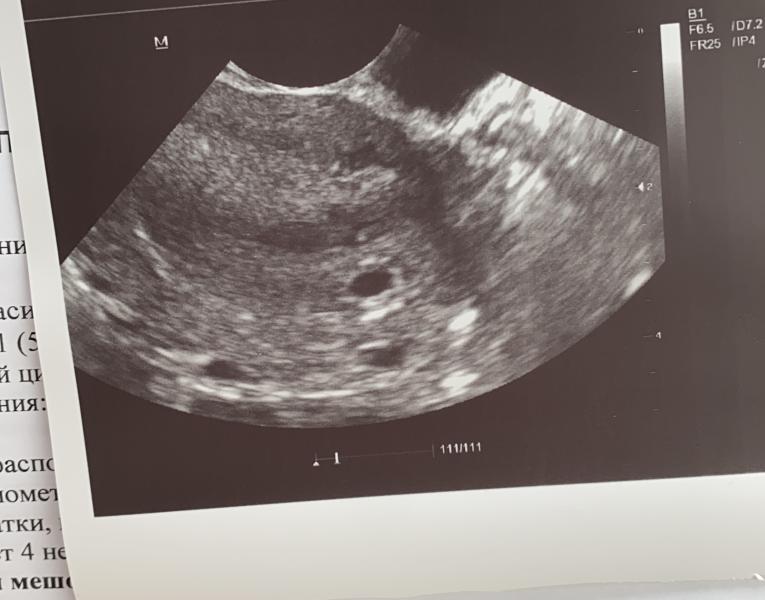

Повторили узи опять два яйца🙈

Первое фото 5 недель

Второе 4.5

Покидайте свои узи на ранних сроках 🙏

(Спросила у узиста про второе яйцо ничего не сказала, сказала на контроль через 10 дней)